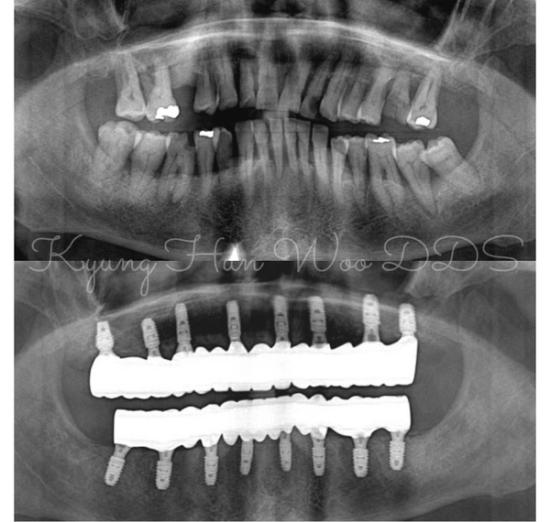

Woo Dental is redefining implant dentistry—crafting the industry’s most desired smiles with exceptional care, premium quality, and accessible pricing